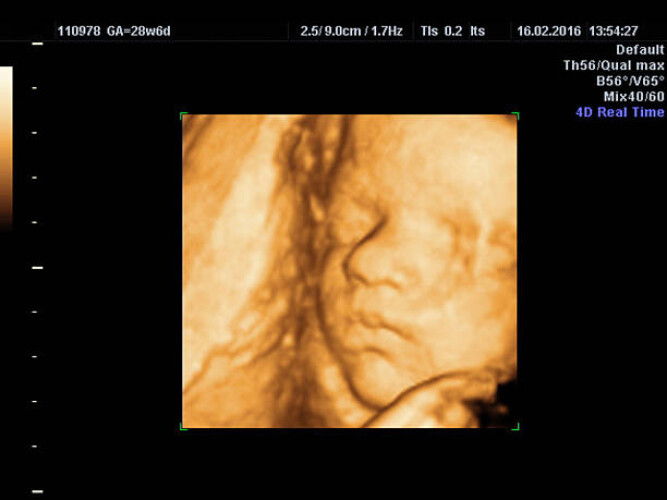

Nakita mo na ba sa ultrasound/sonogram ang itsura ni baby?

ako lang nakakita bawal kasi pumasok c hubby ko nun eh 28 weeks 2d lang pero kita face nya ☺